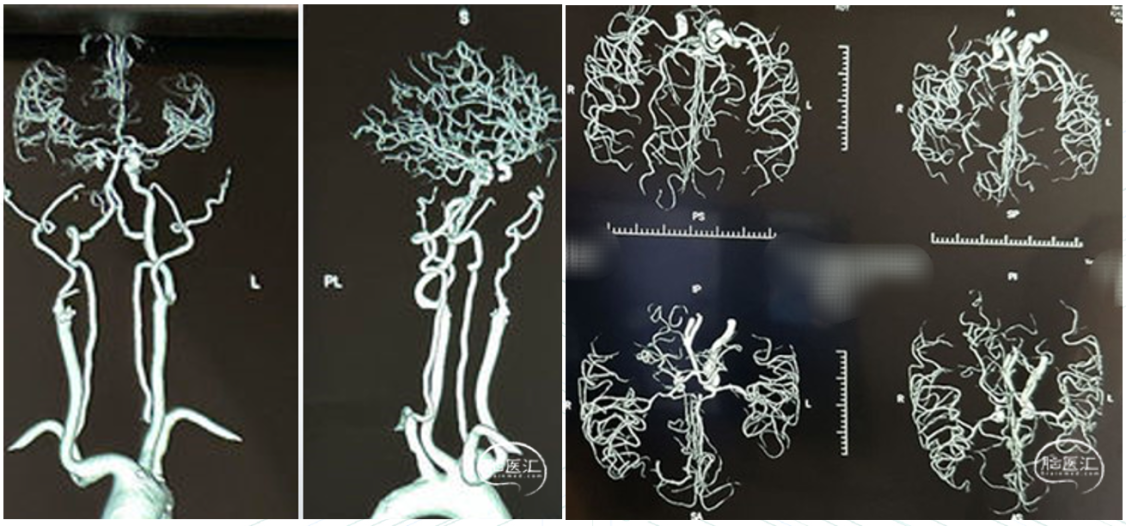

CTA from another hospital indicated Right internal carotid artery occlusion.

Right femoral artery access was obtained, and an 8F femoral sheath was inserted. Angiography revealed complete occlusion of the right ICA from the C1 segment to the intracranial portion. Collateral circulation to the right ICA territory was provided via the ophthalmic artery from the right external carotid artery. The anterior communicating artery was not visualized. The vertebral artery supplied the ICA territory through the posterior communicating artery.